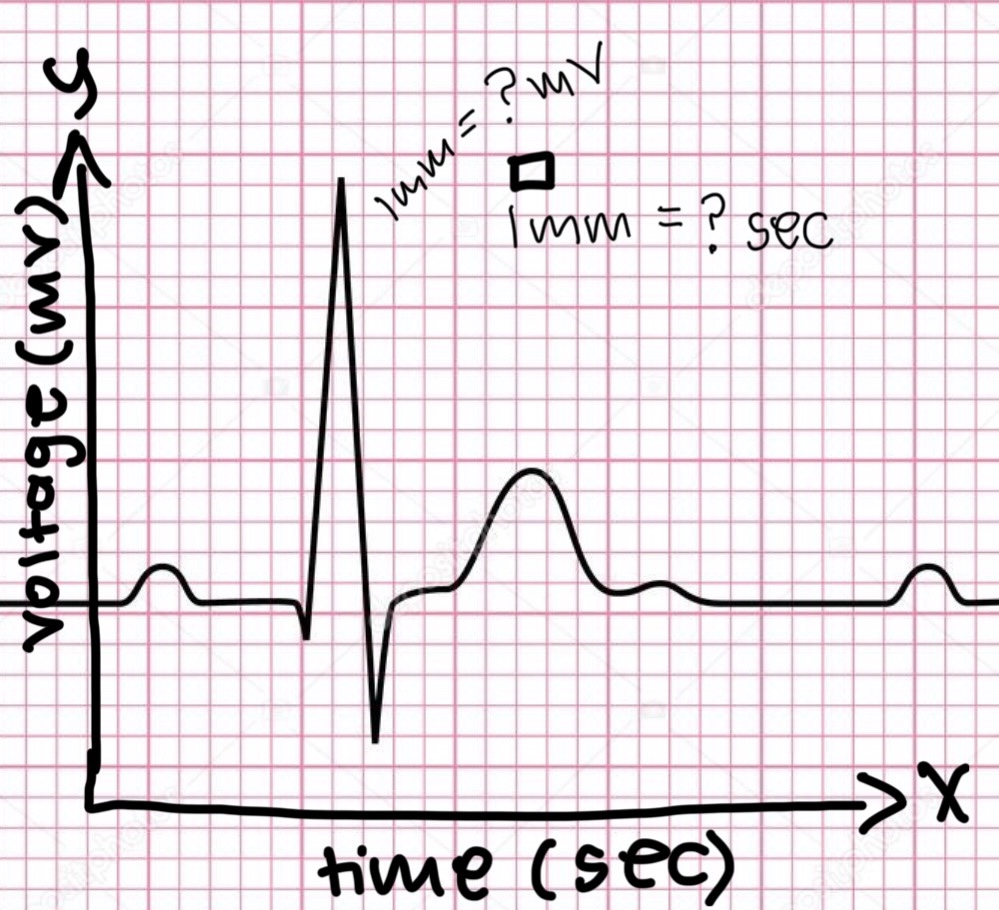

P wave

atrial depolarization

Precedes atrial contraction

QRS complex

ventricular depolarization

Precedes ventricular contraction

T wave

ventricular repolarization

PR interval

Name #1

QRS interval

Name #2

QT interval

Name #3

TP interval

Name #4

PR interval

time from beginning of the P wave to the beginning of the QRS complex

QRS interval

Time from beginning of the QRS complex to the end of the QRS complex

QT interval

Time from beginning of QRS complex to the end of the T wave

TP interval

Time from end of T wave to the beginning of P wave

RR interval

Distance from the peak of one R wave to the peak of the next

0.04

The x axis is time in seconds.

1 mm equals……. seconds?

0.1

The y axis is voltage in mV.

1mm equals ….. mV?

HR = 1500/x mm

Equation for HR or bpm

20

If the ventricular rate is 75 contraction/minute, what is the RR interval in millimeters (mm)?